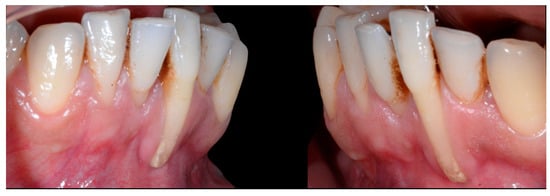

In Figure 6, 11 and 21 show a difference in incisal edge height and gingival margin. Tooth 41 shows gingival recession to the muco-gingival junction (Cairo’s RT1) with root visibility. Tooth 33 had a significant lingual tilt (coronal–lingual torque), not symmetrical to tooth 43.

Figure 6.

Intermediate wire syndrome. Frontal view.

The root of tooth 21 is visible through the gingiva (Figure 7). Figure 8 shows the extent of gingival recession on tooth 41.